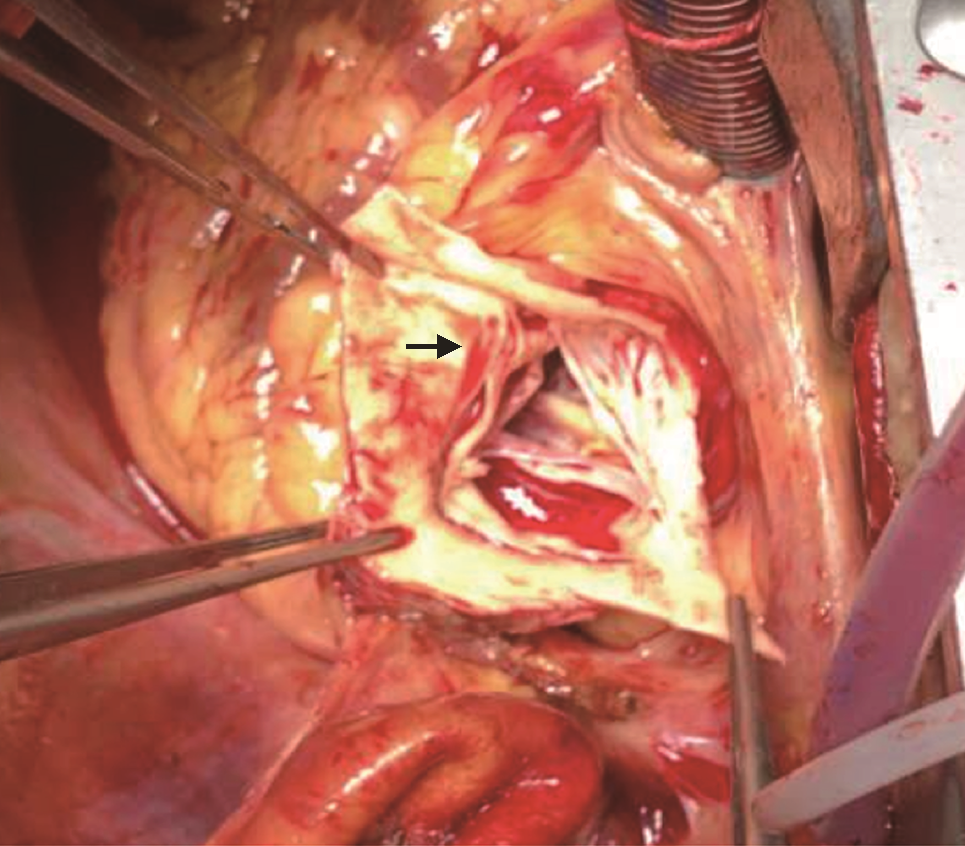

患者入院后血压逐渐恢复至140/85 mmHg,予络活喜控制血压及保肝治疗,患者肝肾功能逐渐好转。5月6日转至心外科全麻下行Bentall手术+主动脉瓣生物瓣置换术(图5)。术后回顾患者主动脉CTA,其主动脉根部冠脉窦水平可见夹层迹象(图6)。